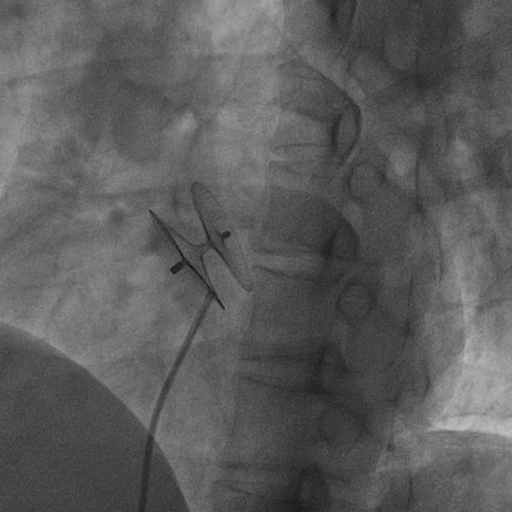

在獲得患者同意后,1月12日,尚福軍主任為患者進行了PFO封堵術。術中造影可見封堵器殘余漏,尚福軍主任用精湛的技藝,順利通過封堵器殘余漏裂縫,將右心導管從右房送入左房,且順利到達肺靜脈;遂行卵圓孔未閉封堵術后殘余漏再次封堵;且完美釋放PFO封堵器,可見兩封堵器呈“馬蹄蓮”狀,再次術中造影未見殘余漏。